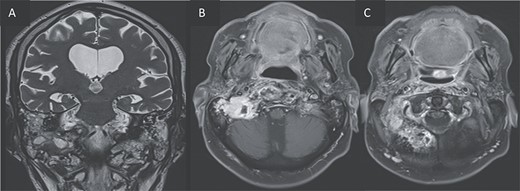

For better diagnostic assessment, the patient underwent a magnetic resonance imaging (MRI) (Figs 3 and 4), it showed the following findings:

An expansile cystic-necrotic lesion localized in the central region of the clivus, characterized by a hypointense rim on T2-weighted images.

Post-gadolinium T1-weighted imaging delineating the cystic center with thick peripheral rim enhancement.

Diffusion-weighted imaging (DWI) and apparent diffusion coefficient (ADC) maps demonstrating central restricted diffusion.

Furthermore, inflammatory changes were noted to extend into the petrous, tympanic, and mastoid segments of the right temporal bone, as well as involving the petrous and mastoid regions of the left temporal bone and the occipital bone. Additionally, small abscess cavities were observed within the right occipital condyle.

T2 coronal (A) and T1 post gadolinium axial images (B, C) showing the extension of the inflammation around the clivus and in the petrous, tympanic, and mastoid portions of the right temporal bone with small abscesses along the mastoid cells and the occipital bone.